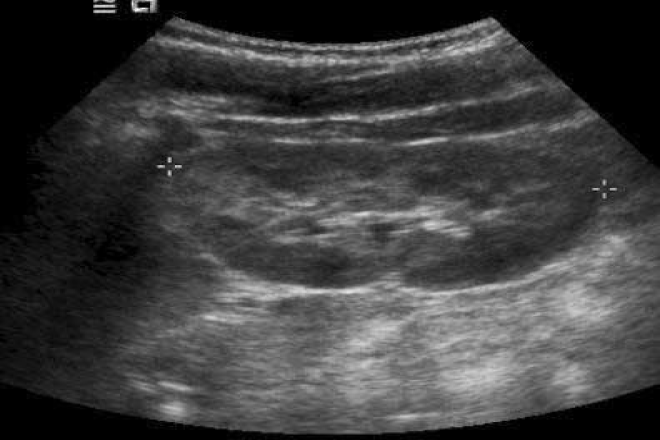

Los cálculos renales son una enfermedad muy común. Los estudios han demostrado que el 15% de las personas forman cálculos renales en algún momento de su vida. Teniendo en cuenta que el 30% de estos pacientes serán hospitalizados y sometidos a alguna intervención (fragmentación endoscópica, por ejemplo) asociada a una reducción de la productividad, se puede valorar el gran impacto social y económico de esta enfermedad.

En las últimas décadas se han producido importantes avances en los métodos de diagnóstico y los tratamientos intervencionistas mínimamente invasivos para poder expulsar una piedra del riñón, conocidas como cálculos renales.